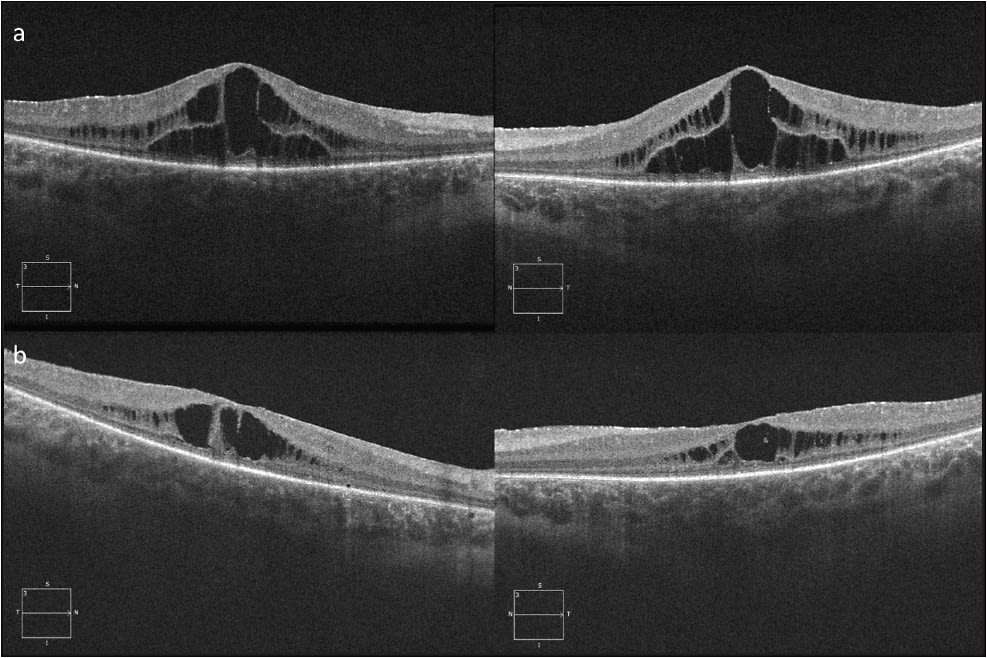

Juvenile X-linked retinoschisis is an early-onset retinal degeneration affecting males. Patients typically present around school age with bilateral mild to moderate central vision loss. Fundus examination shows a spoke-wheel pattern of macular schisis in the inner retinal layers in 98% to 100% of patients (Figure 2). Less than 50% of patients additionally develop peripheral retinoschisis, characterized by a sharply delineated separation of the inner retinal layer usually in the temporal peripheral retina, but it can extend to the macula. Spectral-domain OCT (SD-OCT) has identified that foveomacular schisis occurs due to splitting of the inner nuclear layer (INL) (Figure 2C), and extramacular schisis is present in the INL, outer nuclear layer, and ganglion cell layer.9 The characteristic ERG is “electronegative,” with the a-wave larger than the b-wave.10 Multifocal electroretinography (mfERG) demonstrates widespread central and peripheral cone-system dysfunction.11